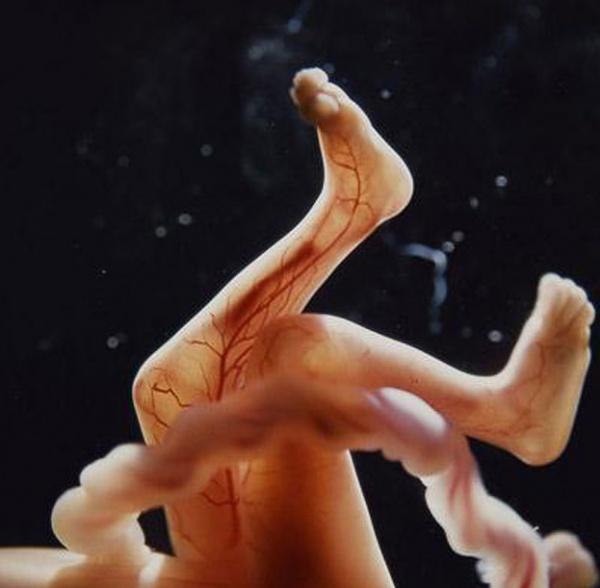

16 εβδομάδων

Οι αρτηρίες του αίματος φαίνονται μέσα από το δέρμα